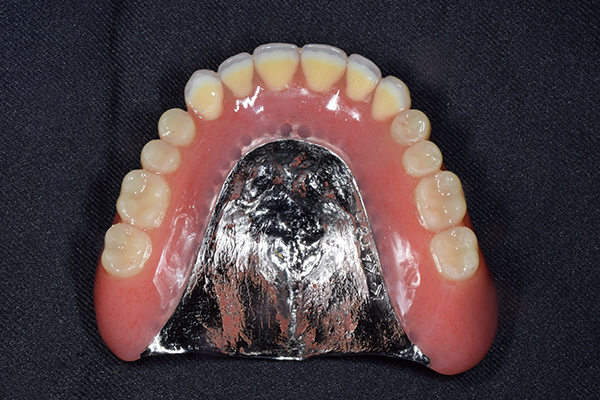

ですのでいざ出来上がってみると見た目が変だったり、噛み合わせがおかしいといったことがでてきやすいのです。 また、左の写真は総入れ歯で自費の入れ歯ですが、このように金属を使うことで入れ歯の厚みを薄くすることができます。

薄くすると、違和感が少ないのと、金属を使うことで、食べ物のの温度を上顎に伝えられるというメリットがあります。 その他、マグネット(磁石)やインプラントを使った入れ歯ですと、パカパカ外れにくいといったことを解消できます。

金属を使用して、薄く違和感が少ない入れ歯が完成しました。 また、見た目にも気を使い、バネが見えにくい様な構造にしました。

入れ歯は極力薄くするために金属を使用しました。しっかり噛める様にするため、ノンメタルクラスプデンチャーにはしませんでした。

上の入れ歯(表)

上の入れ歯(裏)

お口に入っている状態です。嘔吐反射が強かったため、うわあごの部分をくり抜いて作っています。

そのためにはしっかり歯に維持力をかける事、歯茎の部分に圧をかけるため、金属をつかって入れ歯を作成しました。